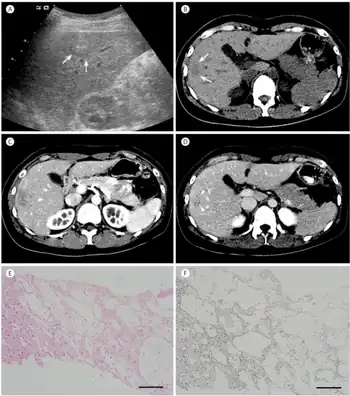

| The CT scan of a patient with peliosis hepatis (left): The follow-up CT (right) after 7 years shows full remission. | |

Peliosis hepatis is an uncommon vascular condition characterised by multiple, randomly distributed, blood-filled cavities throughout the liver. The size of the cavities usually ranges between a few millimetres and 3 cm in diameter.[1] In the past, it was a mere histological curiosity occasionally found at autopsies, but has been increasingly recognised with wide-ranging conditions from AIDS to the use of anabolic steroids. It also occasionally affects spleen, lymph nodes, lungs, kidneys, adrenal glands, bone marrow, and other parts of gastrointestinal tract.[2]

Diagnosis

The condition is typically asymptomatic and is discovered following evaluation of abnormal liver function test. However, when severe, it can manifest as jaundice, hepatomegaly, liver failure, and haemoperitoneum.